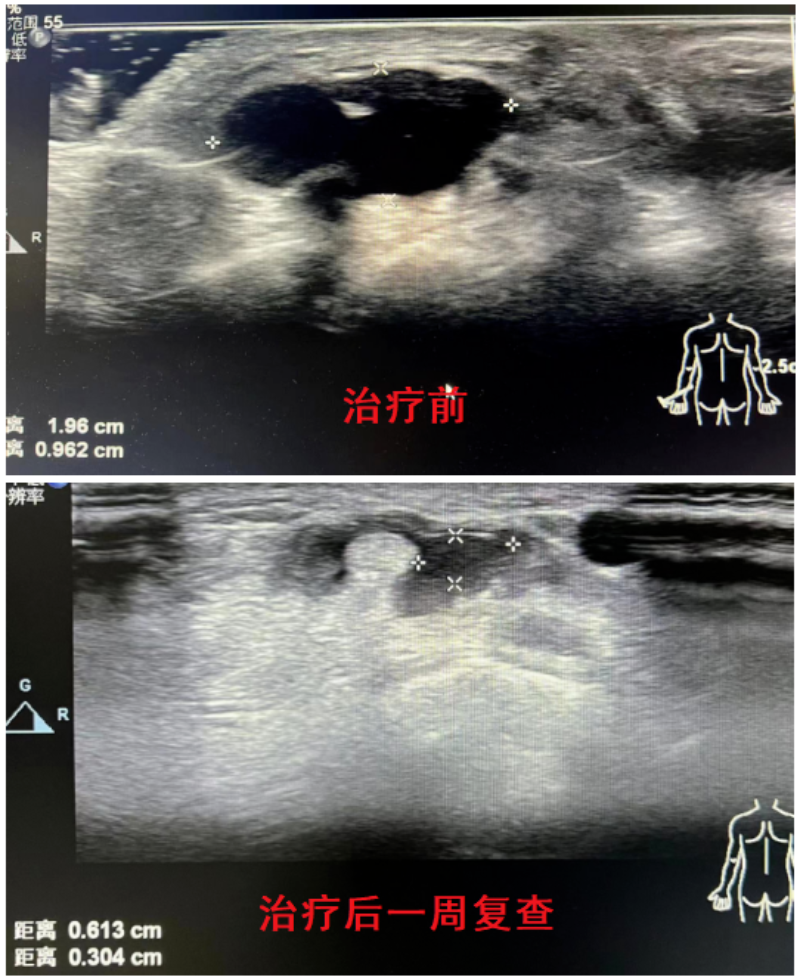

近日我院来了一位患者,发现手腕背侧囊肿半年余,近期伴有手腕酸胀不适。在超声引导下精准穿刺囊腔,抽吸出淡黄色胶冻状囊液,局部压迫症状即刻得到缓解,受到患者及家属的好评。

超声引导下臭氧治疗腱鞘囊肿能精准穿刺,可以安全避开血管、神经等重要组织脏器,行抽吸及药物注射治疗。相比传统外科手术治疗,具有微创、便捷、高效且费用低等优点,无需住院门诊即可快速处理。抽吸注射治疗与手术治疗的复发率几乎相当,可以替代大部分外科手术治疗。